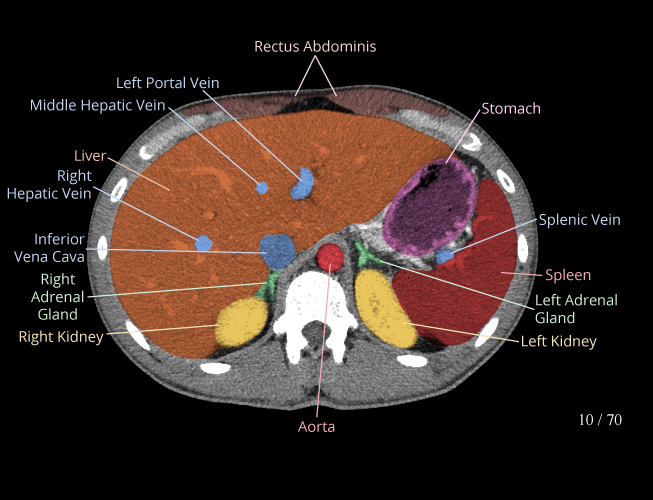

Body

Covers abdominal CT anatomy.